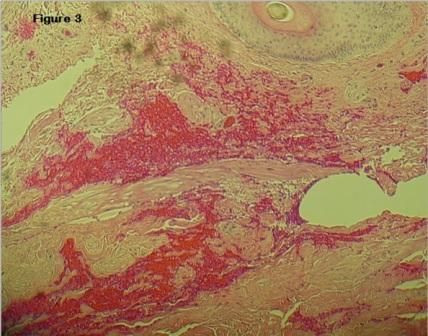

Figure 3. Normal-appearing dermis and epidermis with areas of crystalline deposits. H&E stain, 40X.

A non-contrast CT scan of the abdomen showed partially visualized calcified nodules in his scrotum (Figure 2). The nodules were excised under local anesthesia, and the specimens were sent to pathology. On histologic examination, the dermis and epidermis appeared normal without inflammatory cells or atypia seen in the surrounding tissue (Figure 3). On H&E stain, there were multiple purple crystalline areas without any epithelial lining consistent with calcium deposits (Figure 4). Result of repeated excision of the remaining nodules was consistent with the initial pathology report. Parathyroid scan was normal and ruled out an adenoma.